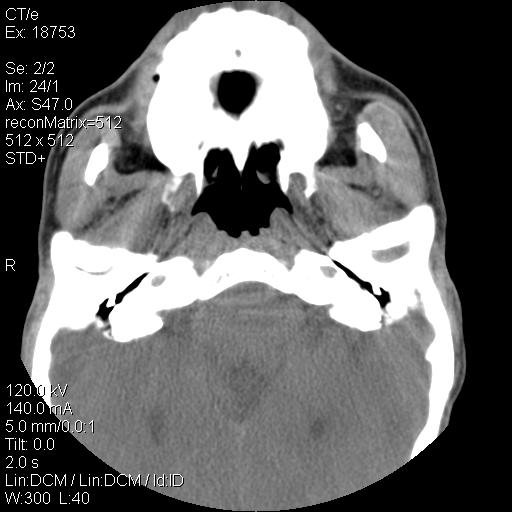

标题: CT21693:男 58岁 右侧咽部疼她2天余 PE:右侧扁桃体肿大 压痛 [打印本页]

标题: CT21693:男 58岁 右侧咽部疼她2天余 PE:右侧扁桃体肿大 压痛

右化脓性扁桃体炎症伴咽后壁脓肿形成.

1 弥漫性肿胀,与周围组织分界清晰,发病急,有明显症状,考虑急性炎症【wbc]

弥漫性肿胀,与周围组织分界不清,发病急,有明显症状,考虑:感染性病变!

结合病史,考虑感染性病变;建议抗炎治疗复查排除肿瘤性病变。